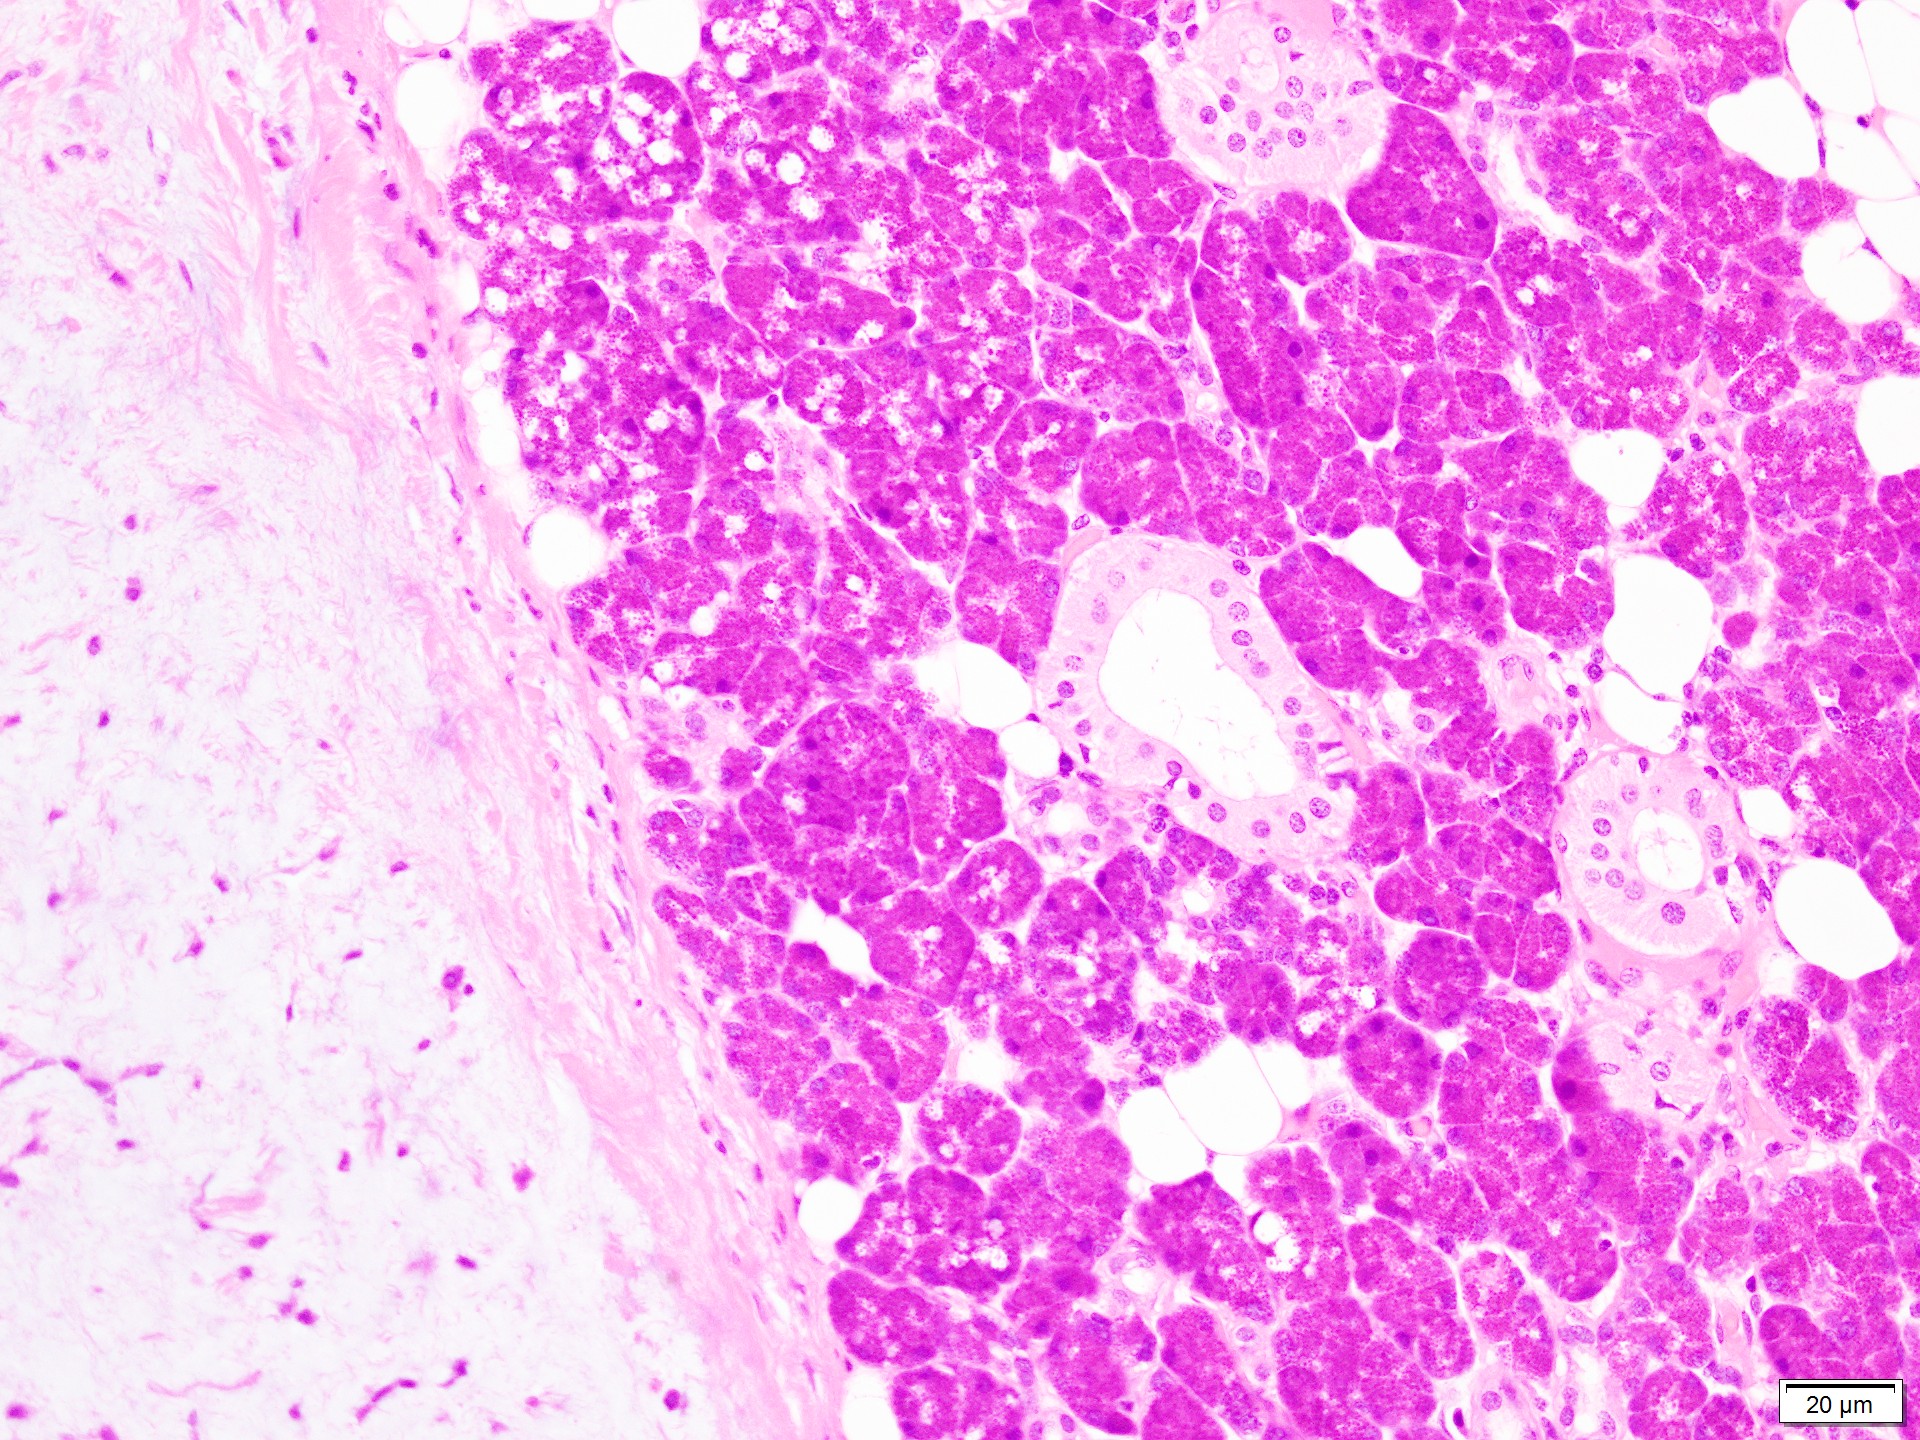

組織標本では、豊富な粘液腫状基質に、星芒状・短紡錘形の筋上皮細胞成分と、管状を示す腺管上皮成分を認める。

腫瘍辺縁には圧排され菲薄化した唾液腺被膜・小葉間結合織を認める。悪性を疑う像は明らかではない。

細胞像弱拡大写真でみられる右側の大きな上皮細胞集塊について質問があったが、腫瘍細胞ではなく腫瘍周囲の腺房細胞で、検体採取時の混入と考える。